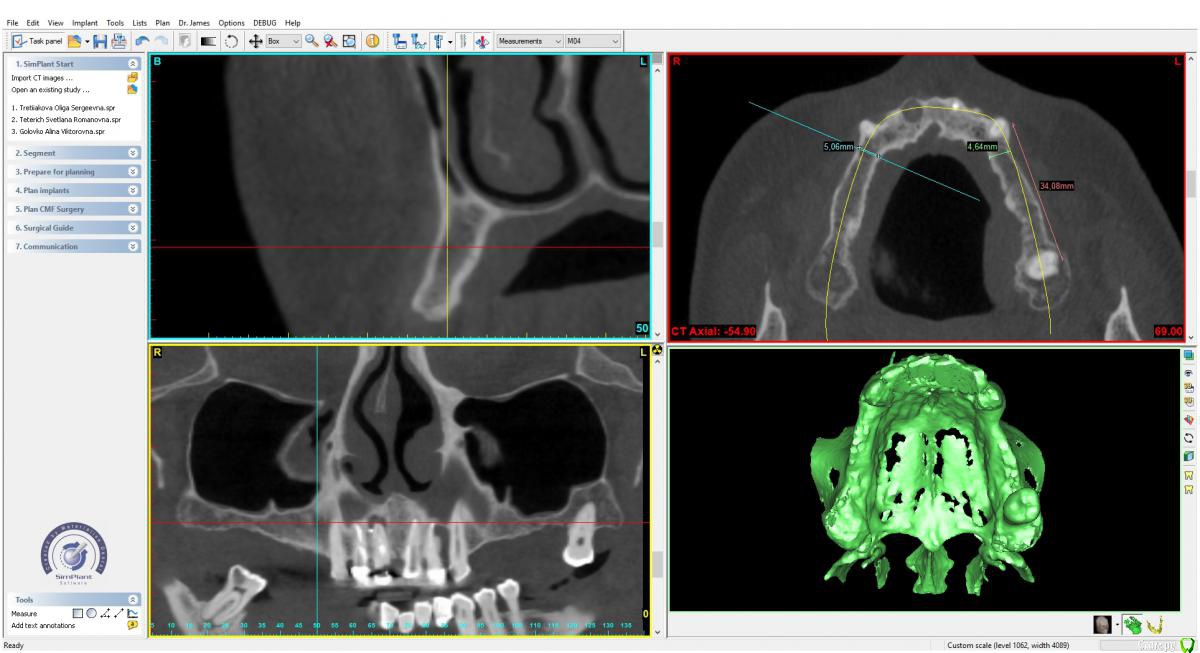

x4ex Опубликовано 28 августа, 2018 Поделиться Опубликовано 28 августа, 2018 (изменено) Здравствуйте, коллеги! Какую методику НКР вы выбрали бы здесь на верхней и нижней челюсти? Варианты: цитопласт, титановая сетка или резорбируемая мембрана (сосидж)? Изменено 28 августа, 2018 пользователем x4ex Ссылка на комментарий

Иван911 Опубликовано 29 августа, 2018 Поделиться Опубликовано 29 августа, 2018 Здравствуйте, коллеги! Какую методику НКР вы выбрали бы здесь на верхней и нижней челюсти? Варианты: цитопласт, титановая сетка или резорбируемая мембрана (сосидж)?tos overview1.jpgtos overview2.jpgЗдравствуйте, я бы выбрал однозначно резорбируемую мембрану, риск осложнений гораздо ниже, а с высотой , вроде как, здесь больших проблем нет. Внутриротовые фото есть ? Ссылка на комментарий

Bier Опубликовано 3 сентября, 2018 Поделиться Опубликовано 3 сентября, 2018 наверху вообще пластика не нужна. Только мягкие ткани. Внизу - надо плясать от протетики, а не тупо смотреть на катешечку. Сделайте виртуальный воск (или реальный), соедините его с КТ (или сделать КТ с рентгенконтрастным шаблоном во рту) поставьте имплантаты относительно будущих коронок на 3мм апикальнее и поймете можно ли спилить гребень или не желательно. 3 Ссылка на комментарий